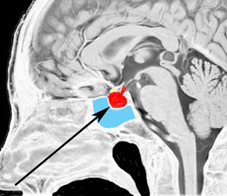

- 下垂体とは脳のほぼ真ん中の底部で視床下部と視交叉(両側の視神経が交叉するところ)の下にある小指の先くらいの小さい組織です

頭蓋骨を透して下垂体腺腫を見たものです。両目の間,頭の中心に緑色に塗ったのが下垂体腺腫です。頭蓋底の鼻腔の奥にあるともいえます。赤い色は動脈,青い色は静脈で,多くの血管に囲まれています。

経蝶形骨洞手術とは

下垂体へ到達するには,黒い矢印のように鼻の孔からのぞいて鼻腔を通って,空色に塗った蝶形骨洞というところを通っていくので,これを経蝶形骨洞手術 transsphenoidal surgery TSSと言います。下垂体腺腫にもっともよく用いられる手術法です。気をつけなければならないのは,海綿状脈洞に伸びている腫瘍を手術で摘出しようと言われたときです。海綿静脈洞内部の手術は開頭手術になることもあり危険性は高いといえます。時には死亡例もあるので手術の内容はしっかり聞いて下さい。